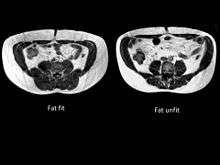

The term TOFI,[1][2] “thin-outside-fat-inside” is used to describe lean individuals with a disproportionate amount of fat (adipose tissue) stored within their abdomen. The figure to illustrate this shows two men, both aged 35 years, with a BMI of 25 kg/m2. Despite their similar size, the TOFI had 5.86 litres of internal fat, whilst the healthy control had only 1.65 litres.

To classify an individual as TOFI, it is essential to measure their internal fat content. The only way that this is possible is by using magnetic resonance Imaging (MRI) or CT scanning. The parameters of the MRI scanner are manipulated to show fat as bright (white) and lean tissue as dark.

The figure clearly shows that despite having an identical waist circumference (in this example all men had a waist of 84 cm), there is considerable variation in the amount of visceral fat (volumes shown on the image in litres) present.

No less important than the TOFI are the metabolic opposites. The subjects have variously been described as being 'FOTI' (fat outside, thin inside), the “metabolically healthy obese” (MHO)[6][7][8][9] or even the fit fat.[10][11] These subjects have little internal fat relative to their size and an example of this can be seen in the figure where MRI images taken at the level of the umbilicus are shown from a fat-fit (FOTI) and a fat-unfit (control) subject.